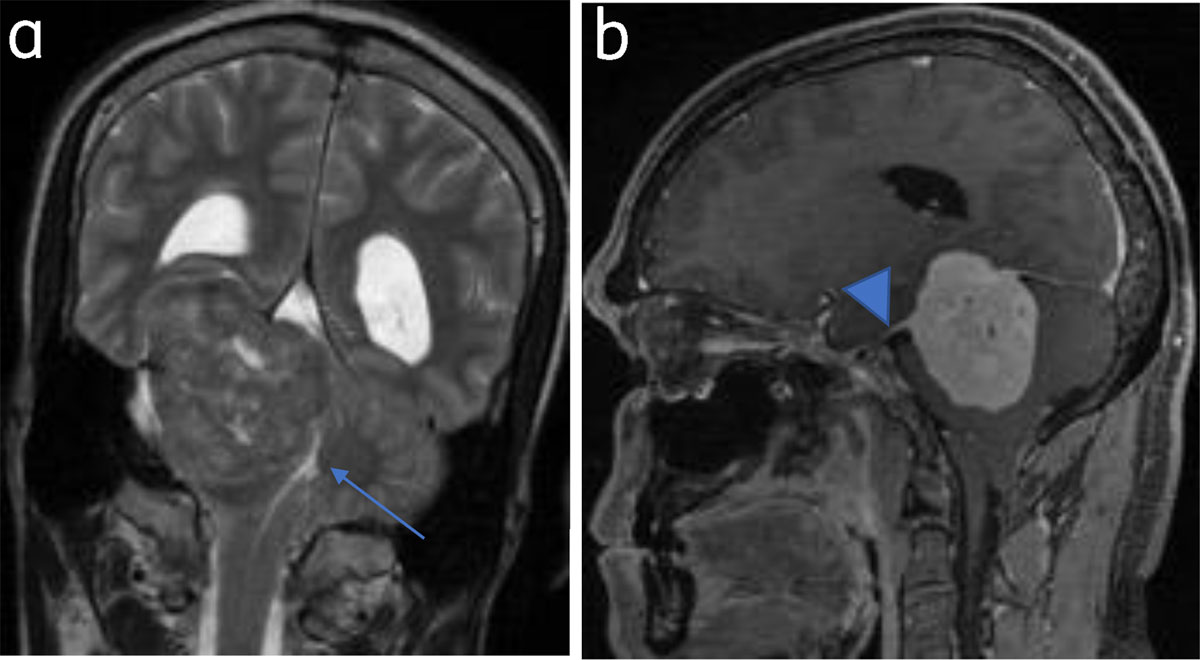

Figure 2

Tentorial meningioma with dural tail: (a) Coronal T2WI tentorial meningioma. Fourth ventricle is effaced (arrow). (b) Sagittal post contrast image shows dural tail (arrowhead).